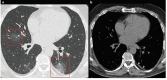

A new type of coronavirus (2019-nCoV) is rapidly spreading worldwide and causes pneumonia, respiratory distress, thromboembolic events, and death. Chest computed tomography (CT) plays an essential role in the diagnosis of viral pneumonia, monitoring disease progression, determination of disease severity, and evaluating therapeutic efficacy. Chest CT can show important clues of 2019-nCoV disease (also known as COVID-19) in patients with an appropriate clinic. Prompt diagnosis of COVID-19 is essential to prevent disease transmission and provides close clinical observation of patients with clinically severe disease. Therefore, radiologists and clinicians should be familiar with the CT imaging findings of COVID-19 pneumonia. Herein, we aimed to review the imaging findings of COVID-19 pneumonia and examine the critical points to be considered for imaging in cases with COVID-19 suspicion.